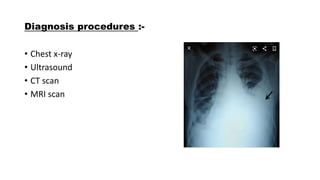

This document discusses haemothorax, which is the presence of blood in the pleural space. It can be caused by trauma, medical issues like pulmonary embolism, or iatrogenically. Clinical presentation includes chest pain, dyspnea, and reduced breath sounds on the affected side. Diagnosis involves chest x-ray, CT scan, or ultrasound. Treatment depends on the cause but typically involves insertion of a chest tube for drainage. Complications can include clot retention, infection, or effusion. Physiotherapy may include deep breathing exercises, mobilization, and assisted coughing to improve ventilation and clear secretions.